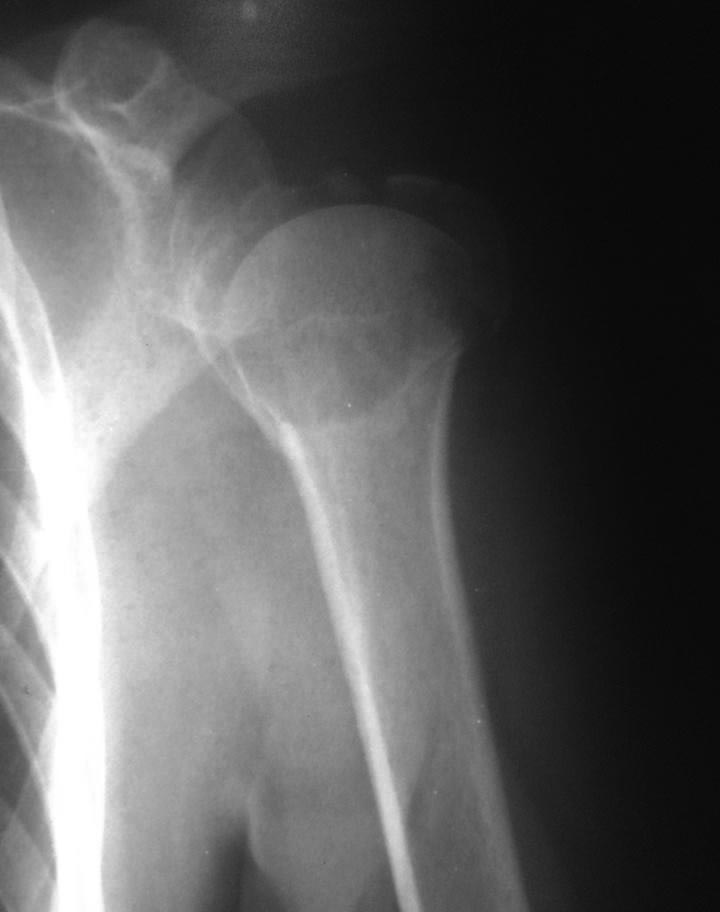

[Ortho] Перелом проксимального метаэпифиза плеча

Дорогие коллеги! Мнение о тактике лечения пациентки в нашем отделении

разделилось.

травма 10 дней назад, падение при катании на обычных лыжах. Сама

врач-рентгенолог 57 лет.

Левая рука, недоминатная. На данный момент ходит в косынке, вся в

сомнениях, что делать.

Мнения по лечению: - ничего не делать - остеосинтез пластиной

блокированной - первичное эндопротезирование (в наличие только геми,

delta не потянет) Может кто-то что более дельное предложит.